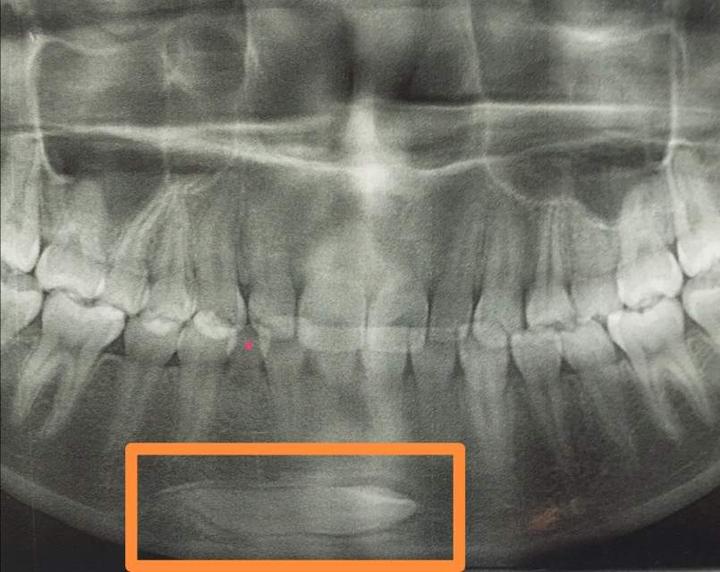

下面三个病例都是因为乳牙龋齿,乳牙滞留,导致对应恒牙阻生。特别提醒:1.重视乳牙龋齿的防治。2.换牙期间6——12岁至少每半年口腔检查一次,及时发现换牙异常,及时干预。

红点处是龋齿滞留的乳牙,方框里是埋伏阻生的恒牙。